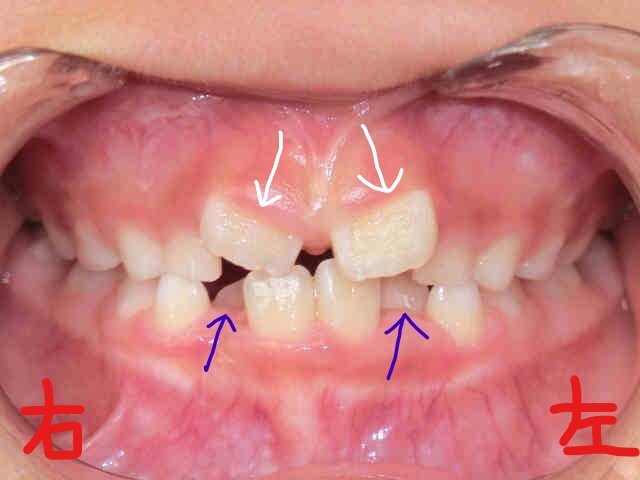

右上の写真は2017年8月時点の同様の正面写真です。やはり下顎前歯(青色矢印)が前方に整列され、上顎前歯(白色矢印)の「八の字」状の萌出が改善されつつあるようすがうかがえます。

当院、みらい歯科・矯正歯科クリニック では、取り外し式の筋機能矯正装置(例:〈マイオブレイス〉、〈K1〉、〈プレオルソ〉)をお使いいただき、日中1〜2時間および就寝時に装着していただきました。同時に、あいうべ体操など代表的な口腔筋機能療法(MFT)を継続して実践していただいた結果、矯正開始後わずか6か月という短期で歯並びが劇的に改善されたのがご覧いただけると思います。

なお、治療期間は6か月(現在治療中)、来院回数は6回、治療費は調整料を含めて336,960円(税込)でした。